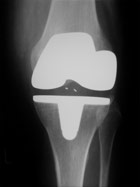

Röntgen nach Kniegelenksprothese

Doppelschlitten

Es stehen sogenannte „Uni-Schlitten“ oder „Doppelschlitten“ zur Verfügung, mit deren Hilfe der defekte Knorpelanteil im Sinne eines Oberflächenersatzes „überzogen“ wird. Der „Uni-Schlitten“  kommt zum Einsatz, wenn nur ein Teil des Kniegelenks künstlich ersetzt werden soll. Die restlichen Bereiche des Kniegelenks sind noch unbeschädigt. Der „Doppelschlitten“ kommt zum Einsatz, wenn mehrere Gelenkabschnitte des Knies von Arthrose betroffen sind. Hierbei wird die gesamte Gelenkoberfläche ersetzt.